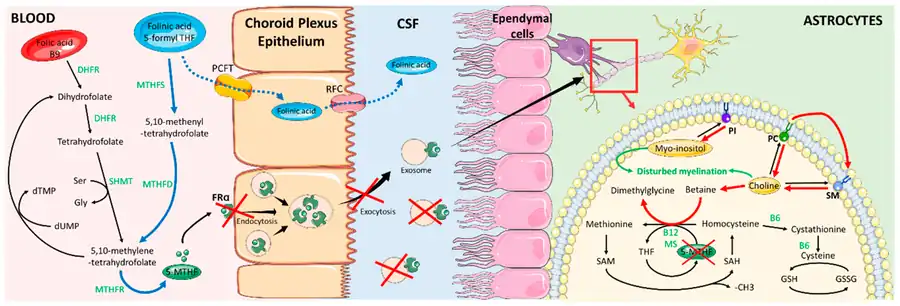

One cause of cerebral folate deficiency is due to a genetic mutation in the FOLR1 gene. It is inherited in an autosomal recessive manner.[2] The mutation of the FOLR1 gene causes an inability to produce the FRA protein.[12] More commonly, CFD involves the malfunction and disruption of the folate receptor alpha (FRA). One way the FRA can be disrupted is by the attachment of the autoantibodies, causing dysfunction in the receptor. Also, a mitochondrial disease can impact the functioning of the folate receptor alpha. In order for the receptor to function properly, energy from the mitochondria is required. Folate must be actively transported into the brain, so ATP from the mitochondria is essential. If the individual has a mitochondrial disease, the FRA could be lacking adequate energy, resulting in the deficiency of folate in the brain.[12]

Other causes appear to be Kearns–Sayre syndrome[5] and autoantibodies to the folate receptor.[6][7][8] Furthermore, secondary cerebral folate deficiency can develop in patients with other conditions. For example, it can develop in AADC deficiency through the depletion of methyl donors, such as SAM and 5-MTHF, by O-methylation of the excessive amounts of L-dopa present in patients.[14][15]